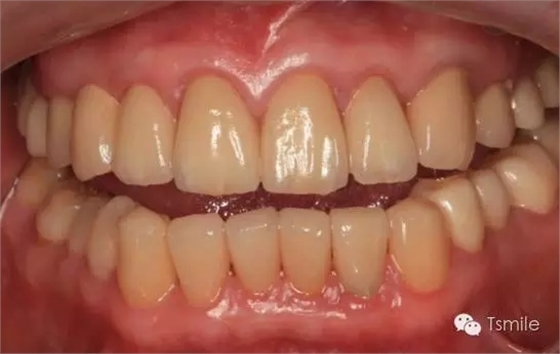

圖6:最終修復(fù)體完成 來(lái)源于tsmlie